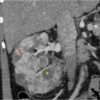

– Ung thư biểu mô tế bào sáng (Clear cell renal carcinoma): chiếm 75% ung thư tế bào thận, tỷ lệ nam nữ là 2:1, khối u phát triền từ tế bào ống lượn gần. Vi thể: sự quá sản dạng hạt nho của tế bào có bào tương sáng, thường kích thước lớn, nhiều cạnh với một nhân trung tâm, bào tương chứa nhiều glycogen và mỡ. Gồm nhiều loại tế bào: tế bào sáng, tế bào ưa eosin, tế bào hình thoi. Gel đặc trung của ung thư thận tế bào sáng là sự khuyết đoạn của nhánh ngắn NST 3 (-3p) gây nên đột biến về gel, gặp trong 95% các trường hợp.